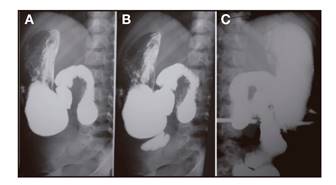

Presentamos el caso de una niña de cinco años, con antecedente de SIC secundario a una resección desde yeyuno proximal a íleon distal realizada a los cuatro años de edad por un vólvulo de intestino medio y malrotación intestinal. La longitud del segmento yeyuno-ileal remanente era de 21 cm, con válvula ileocecal y colon íntegros. Recibía nutrición parenteral y enteral a través de gastrostomía en su domicilio. En el tránsito digestivo, presentaba dilatación del intestino delgado tras la última porción duodenal y gran antiperistaltismo. El vaciamiento del íleon estaba retrasado. El colon no presentaba alteraciones (Fig. 1)